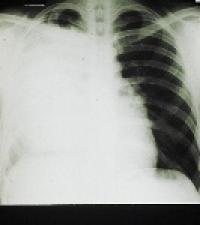

Scientists are looking for non-invasive ways to detect lung cancer in order to reduce the number of patients diagnosed with an advanced stage of the disease.

A multiple marker test in peripheral blood is one such way. In research performed at the IRST Biosciences Laboratory in Italy, researchers looked at blood from 100 healthy donors and blood from 100 patients with non-small cell lung cancer (NSCLC). By using a combination of four specific testing techniques, they could discriminate between healthy donors and NSCLC patients.